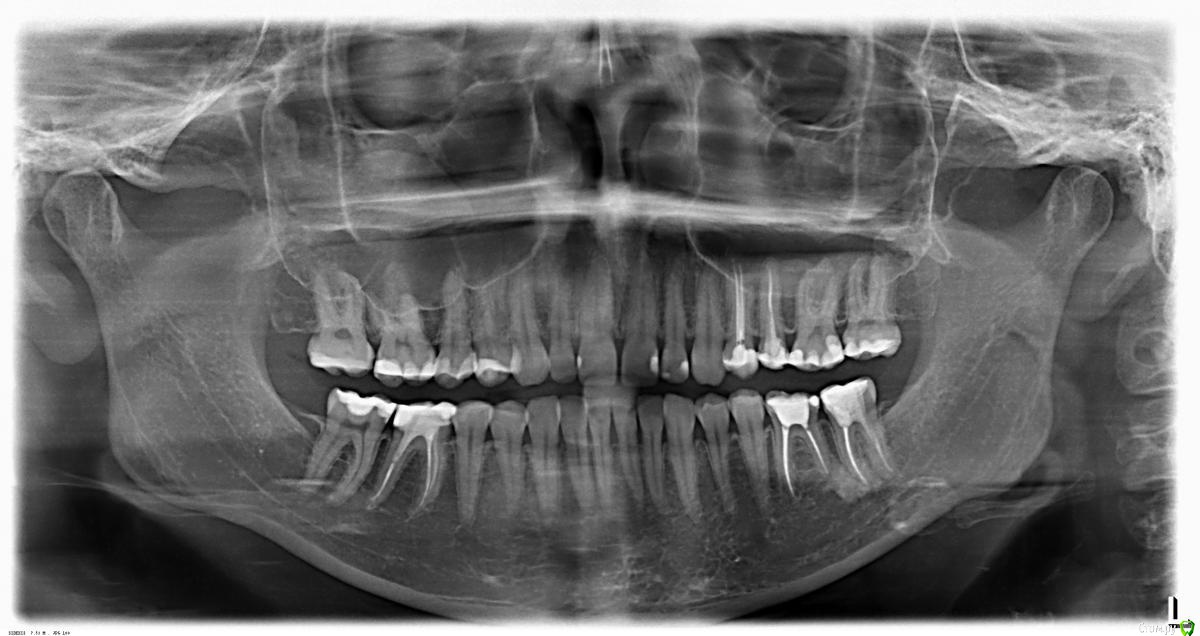

Что можно сказать о состоянии костной ткани по снимку - грозит ли пародонтоз?

Уже лет с 20 начала замечать небольшие "черные треугольники" в районе нижних резцов, но меня лечили только от кариеса и игнорировали мои вопросы по поводу десен, мол, они с возрастом опускаются у всех.

Так ли это - нормально ли состояние моих десен и костной ткани, учитывая возраст?

Не придирайтесь к себе, по снимкам все хорошо.

Рада бы не придираться, но вычитала, что в норме костная ткань идет четко по уровню границ между коронками и корнями зубов. А у меня, насколько мне показалось по снимку, это не так.

К тому же есть случай пародонтоза с потерей зубов у близкого родственника.